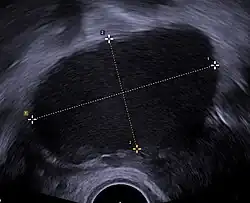

A 2 cm left ovarian cyst as seen on ultrasound

Ovarian cysts are usually diagnosed by pelvic ultrasound, CT scan, or MRI, and correlated with clinical presentation and endocrinologic tests as appropriate.[15] Ultrasound is the most important imaging modality, as abnormalities seen in a CT scan sometimes prove to be normal in ultrasound.[5][8] If a different modality is needed, then MRIs are more reliable than CT scans.[5]

Usually, an experienced sonographer can readily identify benign ovarian cysts, often with a level of accuracy that rivals other approaches.[5]

Follow-up imaging in women of reproductive age for incidentally discovered simple cysts on ultrasound is not needed until 5 cm, as these are usually normal ovarian follicles. Simple cysts 5 to 7 cm in premenopausal females should be followed yearly. Simple cysts larger than 7 cm require further imaging with MRI or surgical assessment. Because they are large, they cannot be reliably assessed by ultrasound alone; it can be difficult to see posterior wall soft tissue nodularity or thickened septation due to limited ultrasound beam penetrance at this size and depth. For the corpus luteum, a dominant ovulating follicle that typically appears as a cyst with circumferentially thickened walls and crenulated inner margins, follow up is not needed if the cyst is less than 3 cm in diameter.[8] In postmenopausal women, any simple cyst greater than 1 cm but less than 7 cm needs yearly follow-up, while those greater than 7 cm need MRI or surgical evaluation, similar to reproductive age females.[16]